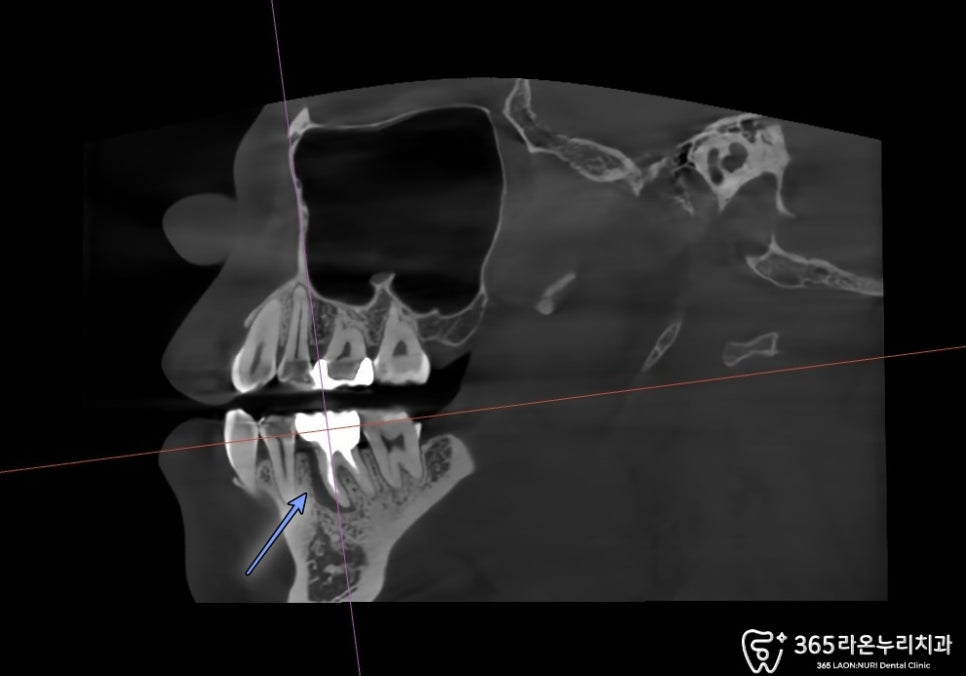

오산대역 치과 에서

CT를 찍어 치조골 두께 및 염증을

확실하게 파악했습니다.

전반적으로 골소실이 매우 심하고

뼈도 많이 녹아있습니다.

식립 후 CT를 확인해 보면

알맞은 위치에 식립이 된

모습을 확인할 수 있었습니다.